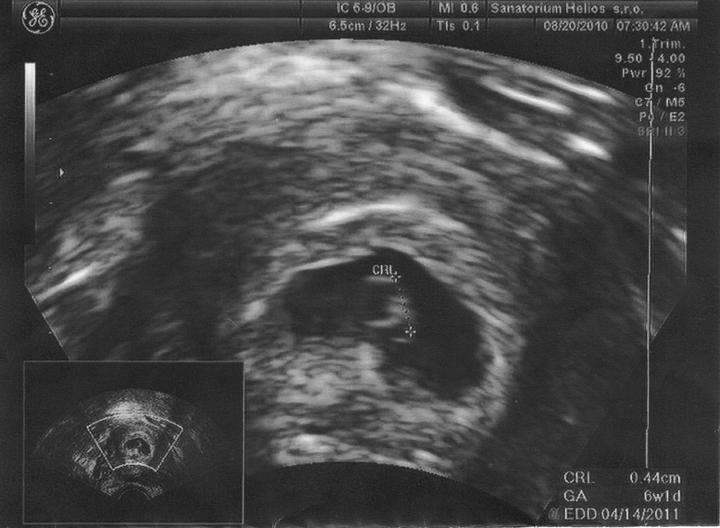

Za 7 hodin uvidíme naši fazolku, nemůžu se dočkat a asi proto nemůžu spát. Strašně se těším. Snad bude vše v pořádku.